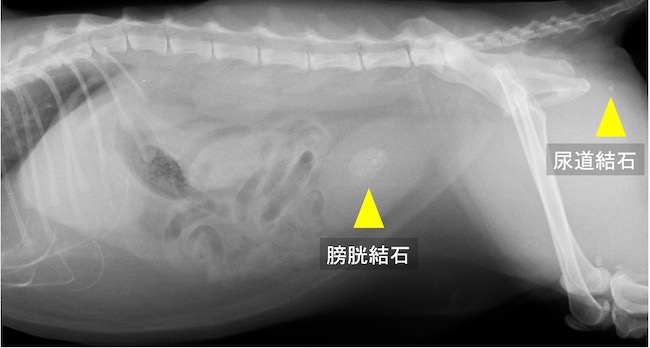

雄猫の膀胱結石および尿道結石。排尿障害により急性腎障害を呈していた。

しかし膀胱結石が尿道に落ちてきてしまうことがあります。

犬・猫に関わらず、メスは尿道が太くて短いので結石が詰まりにくいですが、オスは尿道が細くて長いため結石が詰まりやすいです。

結石が尿道に詰まった場合は排尿ができないために急性腎障害になる可能性があり、その場合は命に関わります。